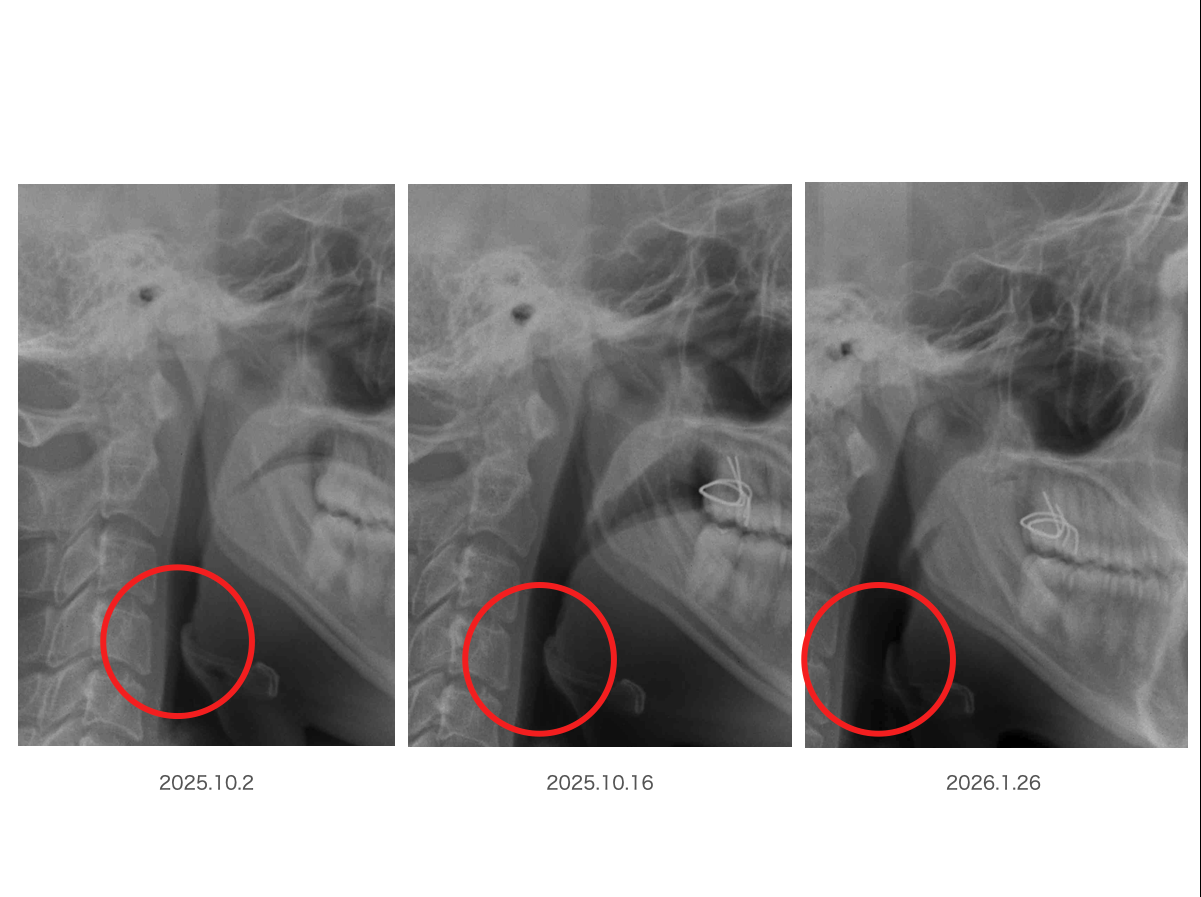

では赤丸で囲ってみましょうか?

顎が前に出たからなのでしょうか?

実はこの顎が前に出る反応もご本人の意思とは関係なく反射的に起こっています